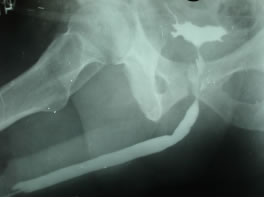

- Восходящая уретрография - остановка

контраста в бульбозном отделе уретры.